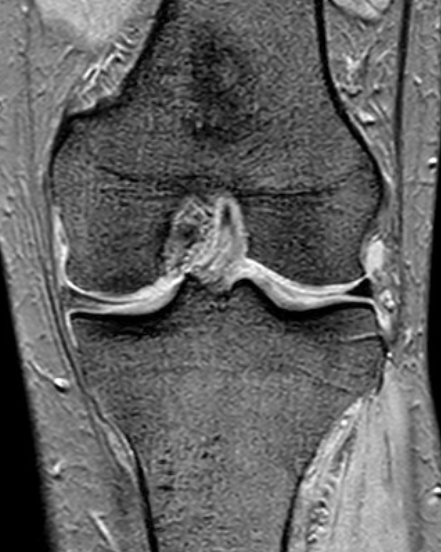

MRI所見

変形性膝関節症 グレード2

内側半月板断裂

軟骨擦り減り(内>外)